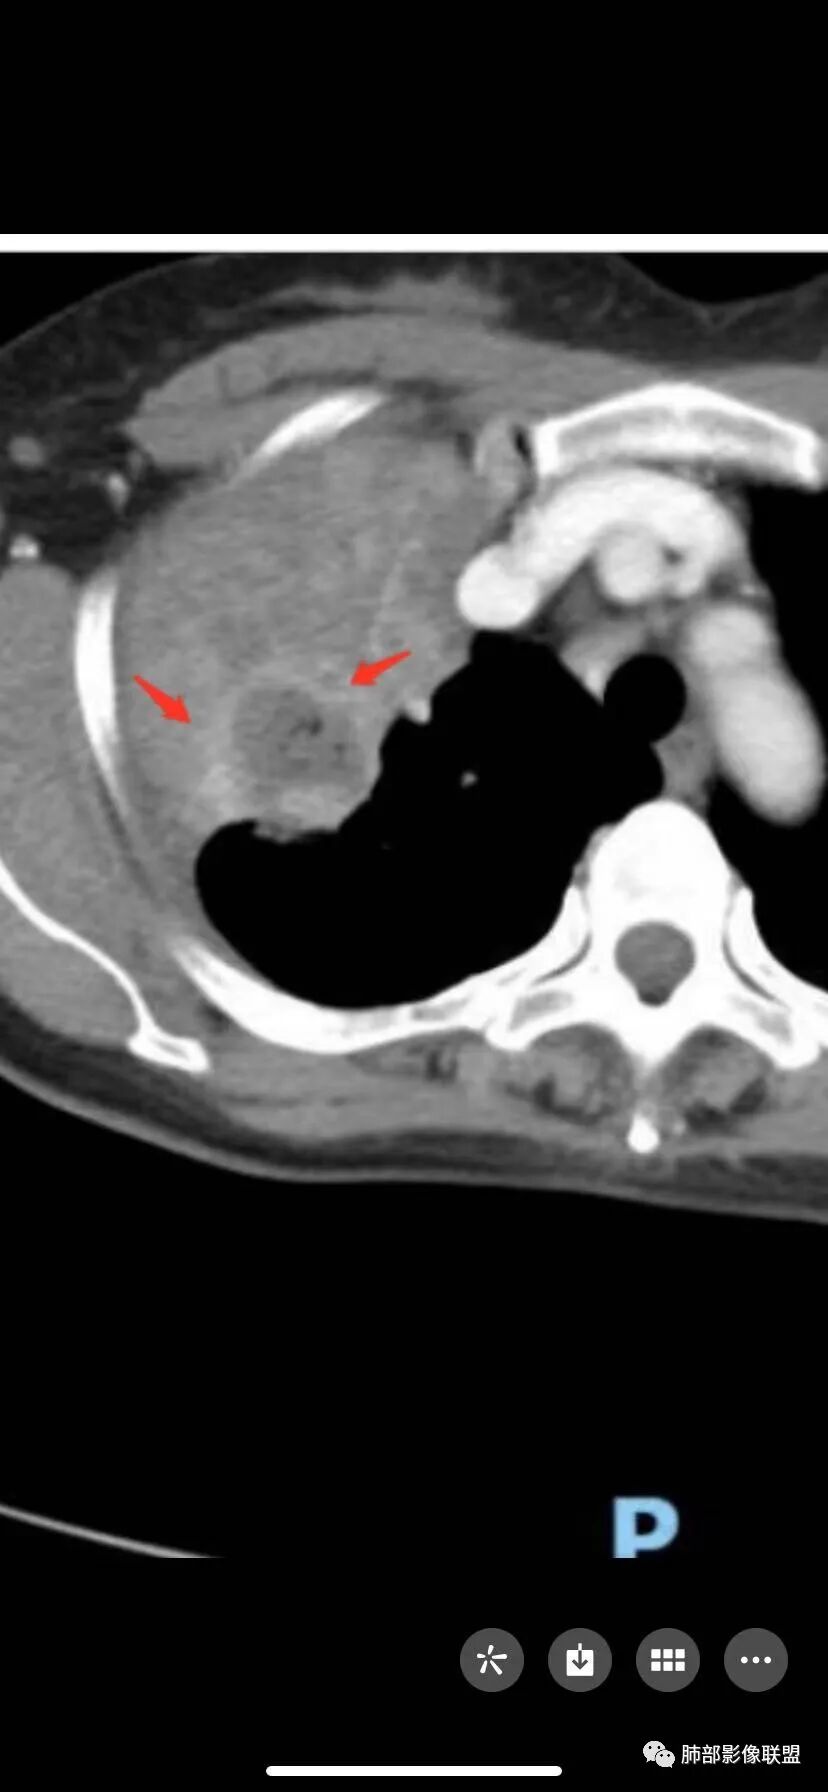

两个病灶独立,又有关联性,内侧病灶近端的支气管包绕在外侧病灶之中,但是走形自然

内部大片坏死区,其中还有不规则空洞

坏死腔内壁清,有强化环

肺动脉在实变区走形自然,坏死腔周围受压推移,走形自然,坏死区内破坏

这类坏死区内空洞,提示坏死液比较粘稠

不是液化坏死,液化坏死,这么大,有气体进来按理会形成液气平面

凝固性坏死